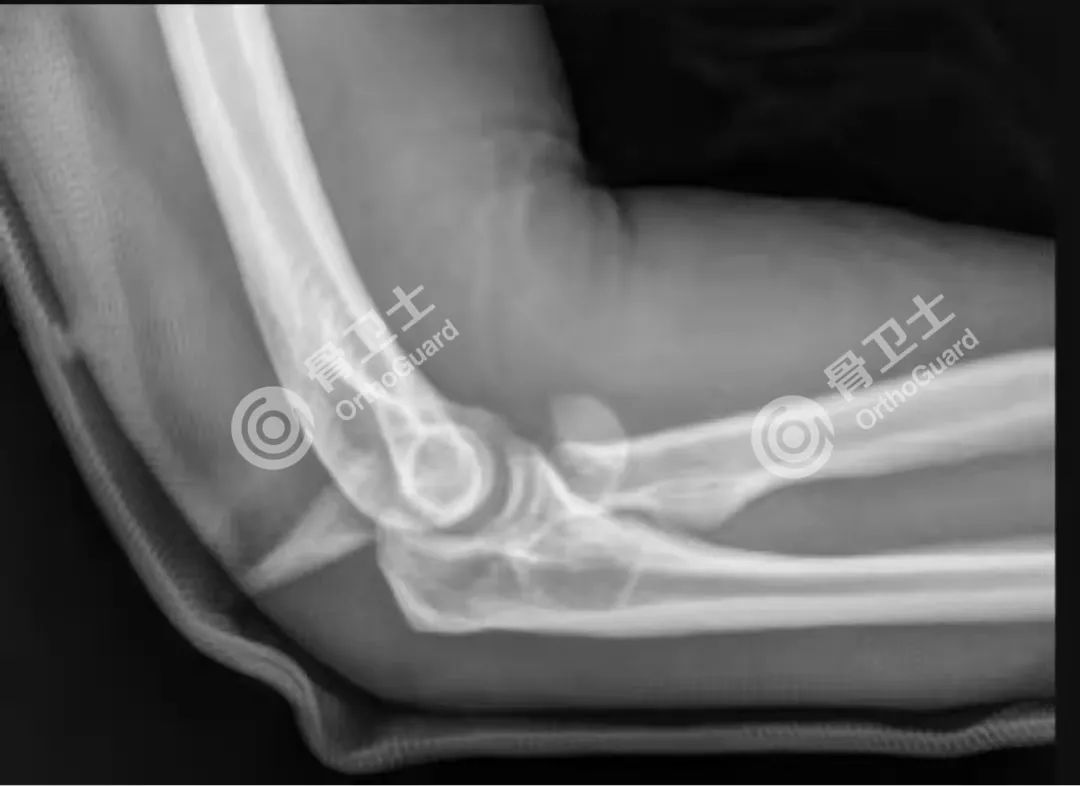

▲术前影像资料

这是一位38岁的男性患者,因意外在家中踩空从二楼摔伤,入院后经详细查体发现右肩外侧疼痛、活动受限,右肘部畸形,肿胀明显,压痛明显,右侧肱动脉未及,右肘活动受限,右手大拇指轻度麻木,右手中指环指小指麻木;经X线检查诊断为右桡骨小头粉碎性骨折,无法应用骨折固定的方式来修复,关节面严重破坏,肘关节活动障碍,这在骨科是一个非常让人棘手的问题,稍有不慎就会导致肘关节功能障碍。考虑患者年纪尚轻,经过科室反复研究讨论,建议患者实施右桡骨小头置换术。主管医师详细的给患者讲解手术的原理、方法及预后相关内容,得到了患者的认可,接受该项手术。